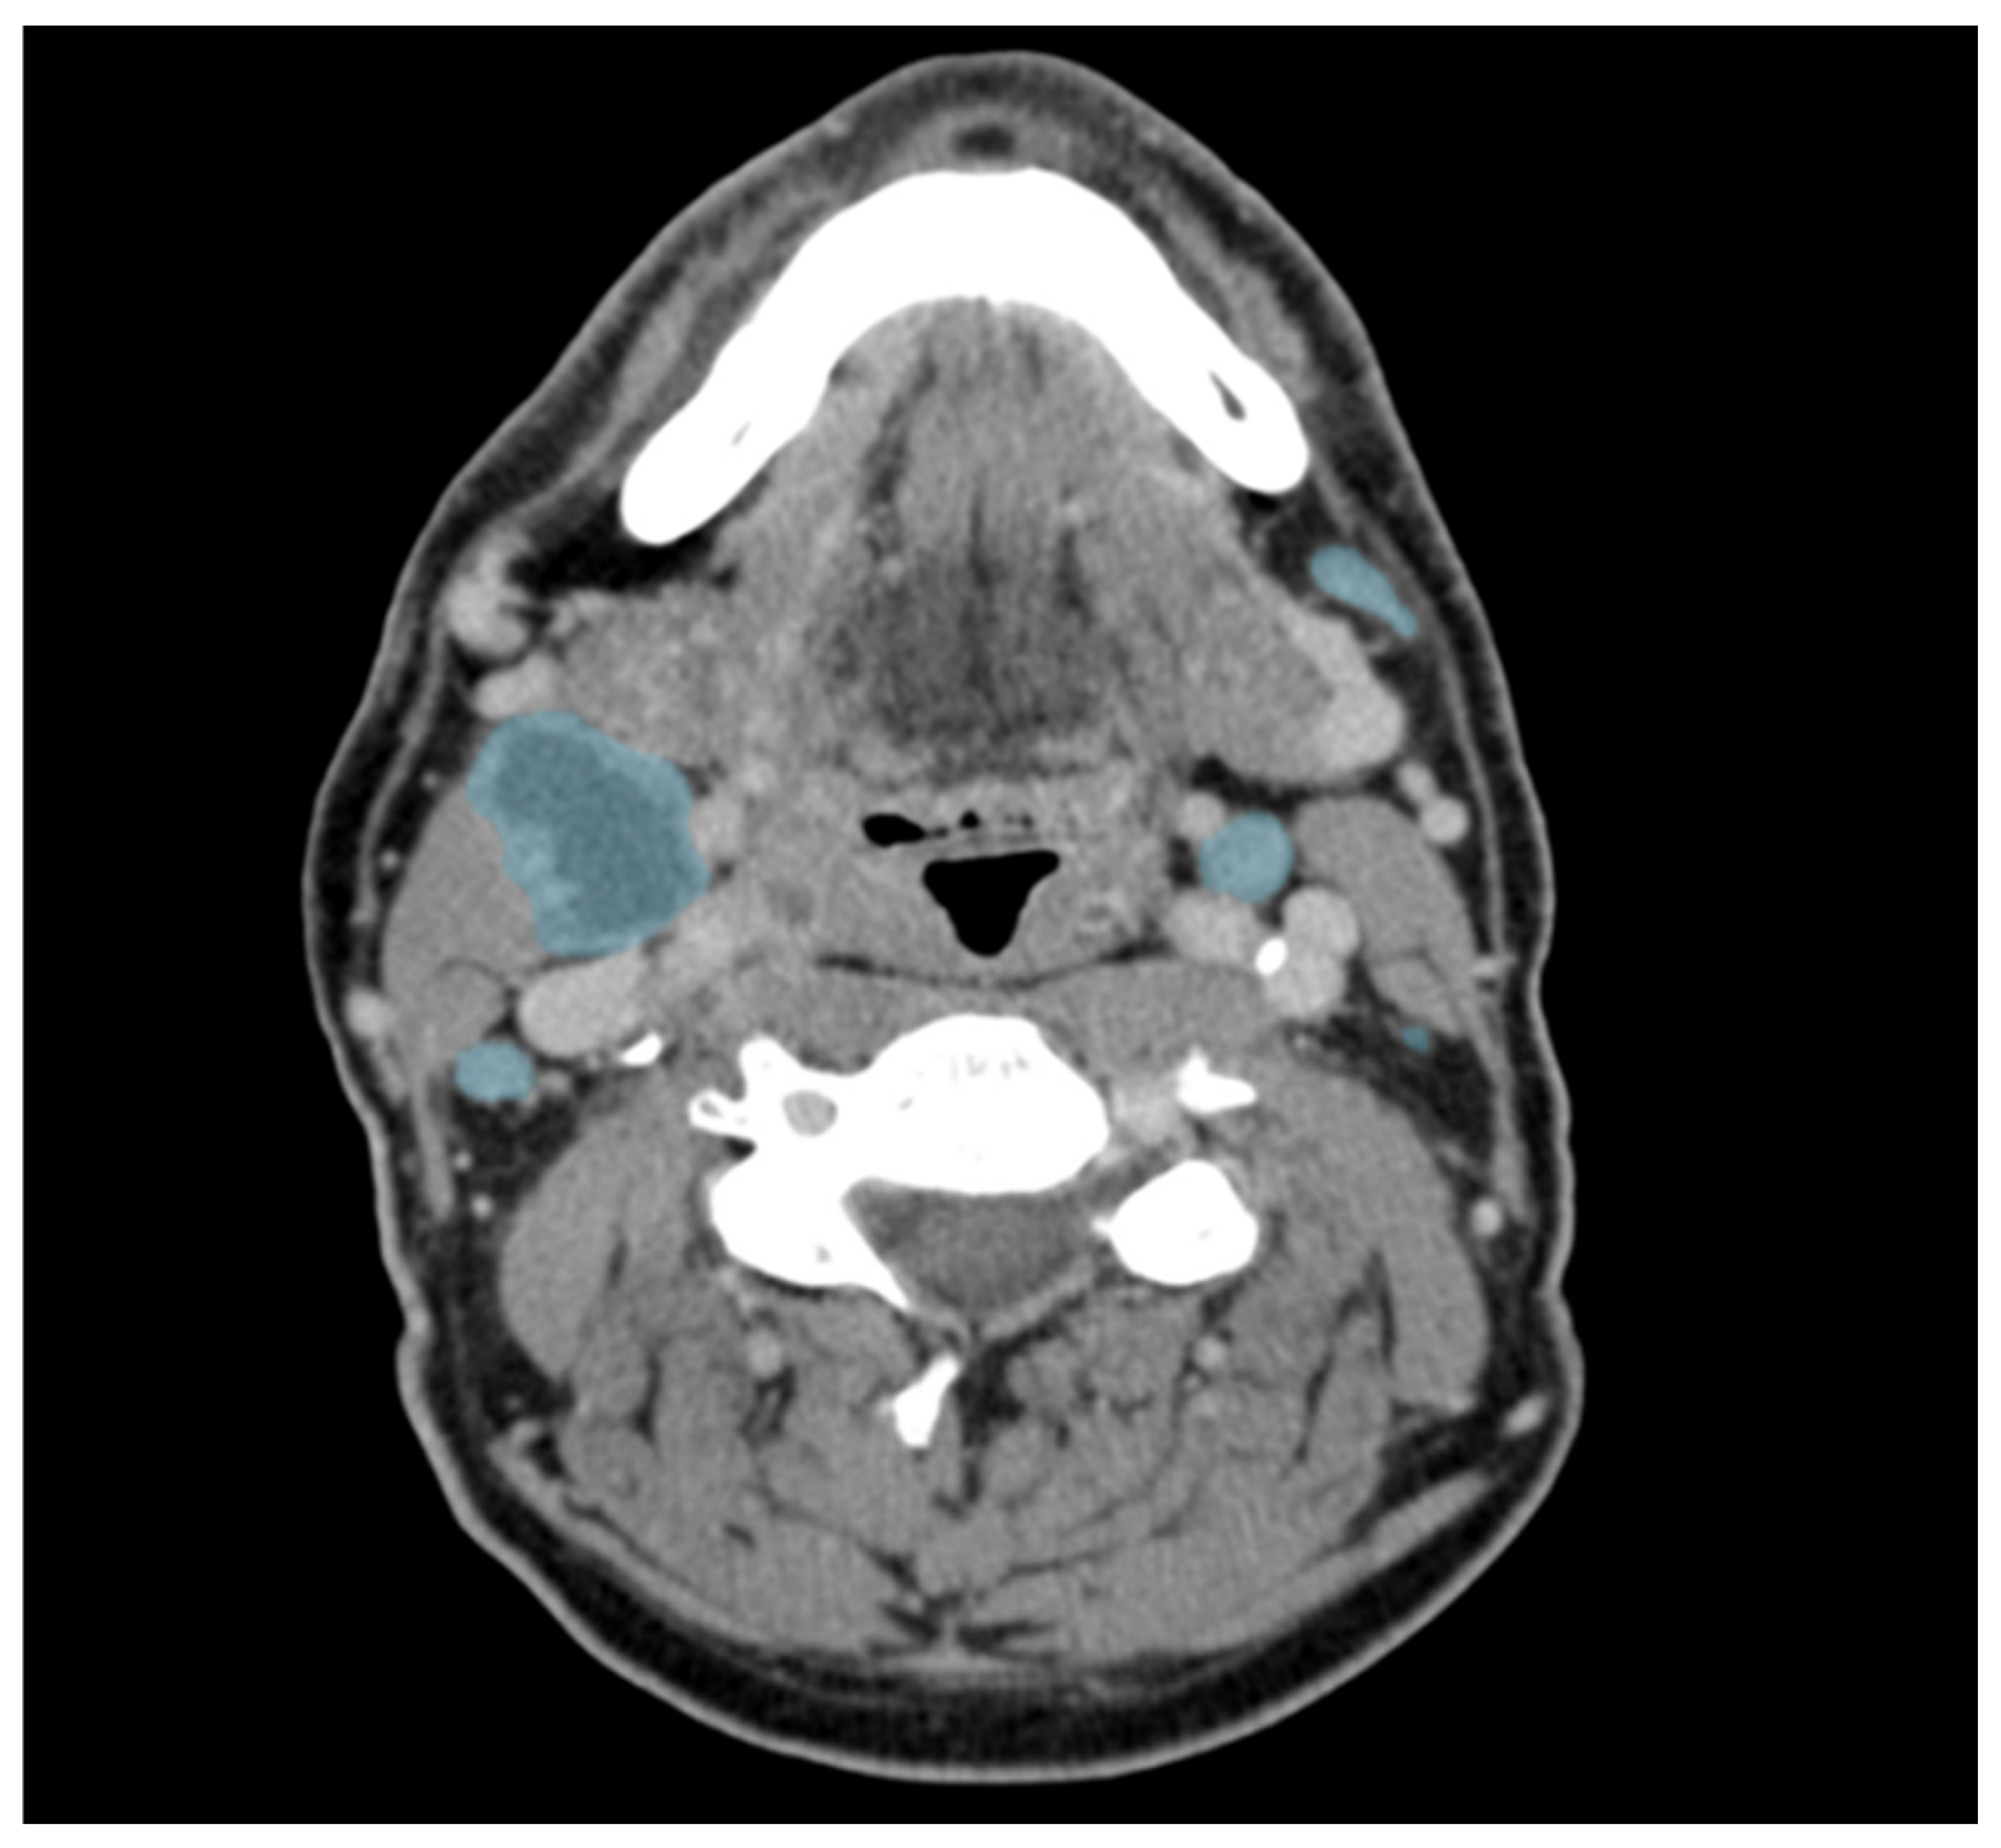

Figure 2 shows an example of the manual segmentation in one CT slice. In comparison to the corrected ground-truth, the preliminary model achieves a recall of 0.66 with a global Dice of 0.74.

Figure 2.

Example of manually corrected lymph node segmentations in an axial contrast-enhanced CT of a patient with head and neck cancer. Lymph nodes are marked in blue. Please note the central necrosis (more hypodense areas) of the large lymph node on the patient’s right.